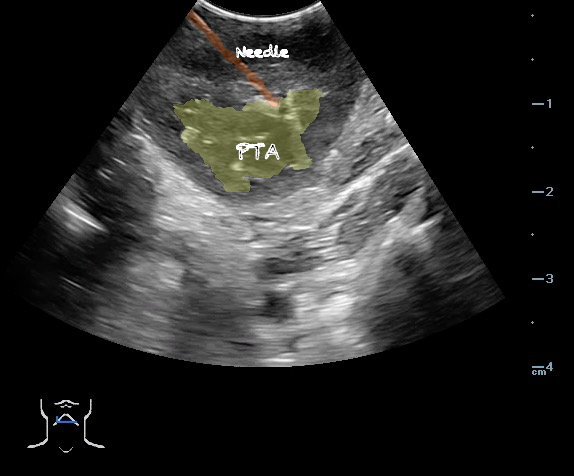

Peritonsillar abscess (PTA)33,34

- Peritonsillar abscess is visualized as a hypoechoic or complex cystic structure

- Ultrasound-guided needle aspiration of a PTA:

- The depth of the abscess cavity from the mucosal surface should be noted to determine the length of the needle required to drain the abscess.

- Figure 45. and 46. PTA aspiration

- The carotid artery is seen as an anechoic tubular structure along the posterolateral aspect of the tonsil on ultrasound. Its relationship to the abscess cavity should be determined. Color Doppler can help locate the carotid artery.

- Figure 47 and 48. PTA with color Doppler of carotid artery